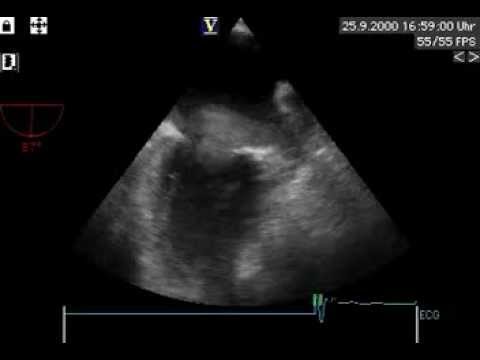

Video 16.2

Video 16.2 Echocardiographic exclusion of alternative cardioembolic sources.